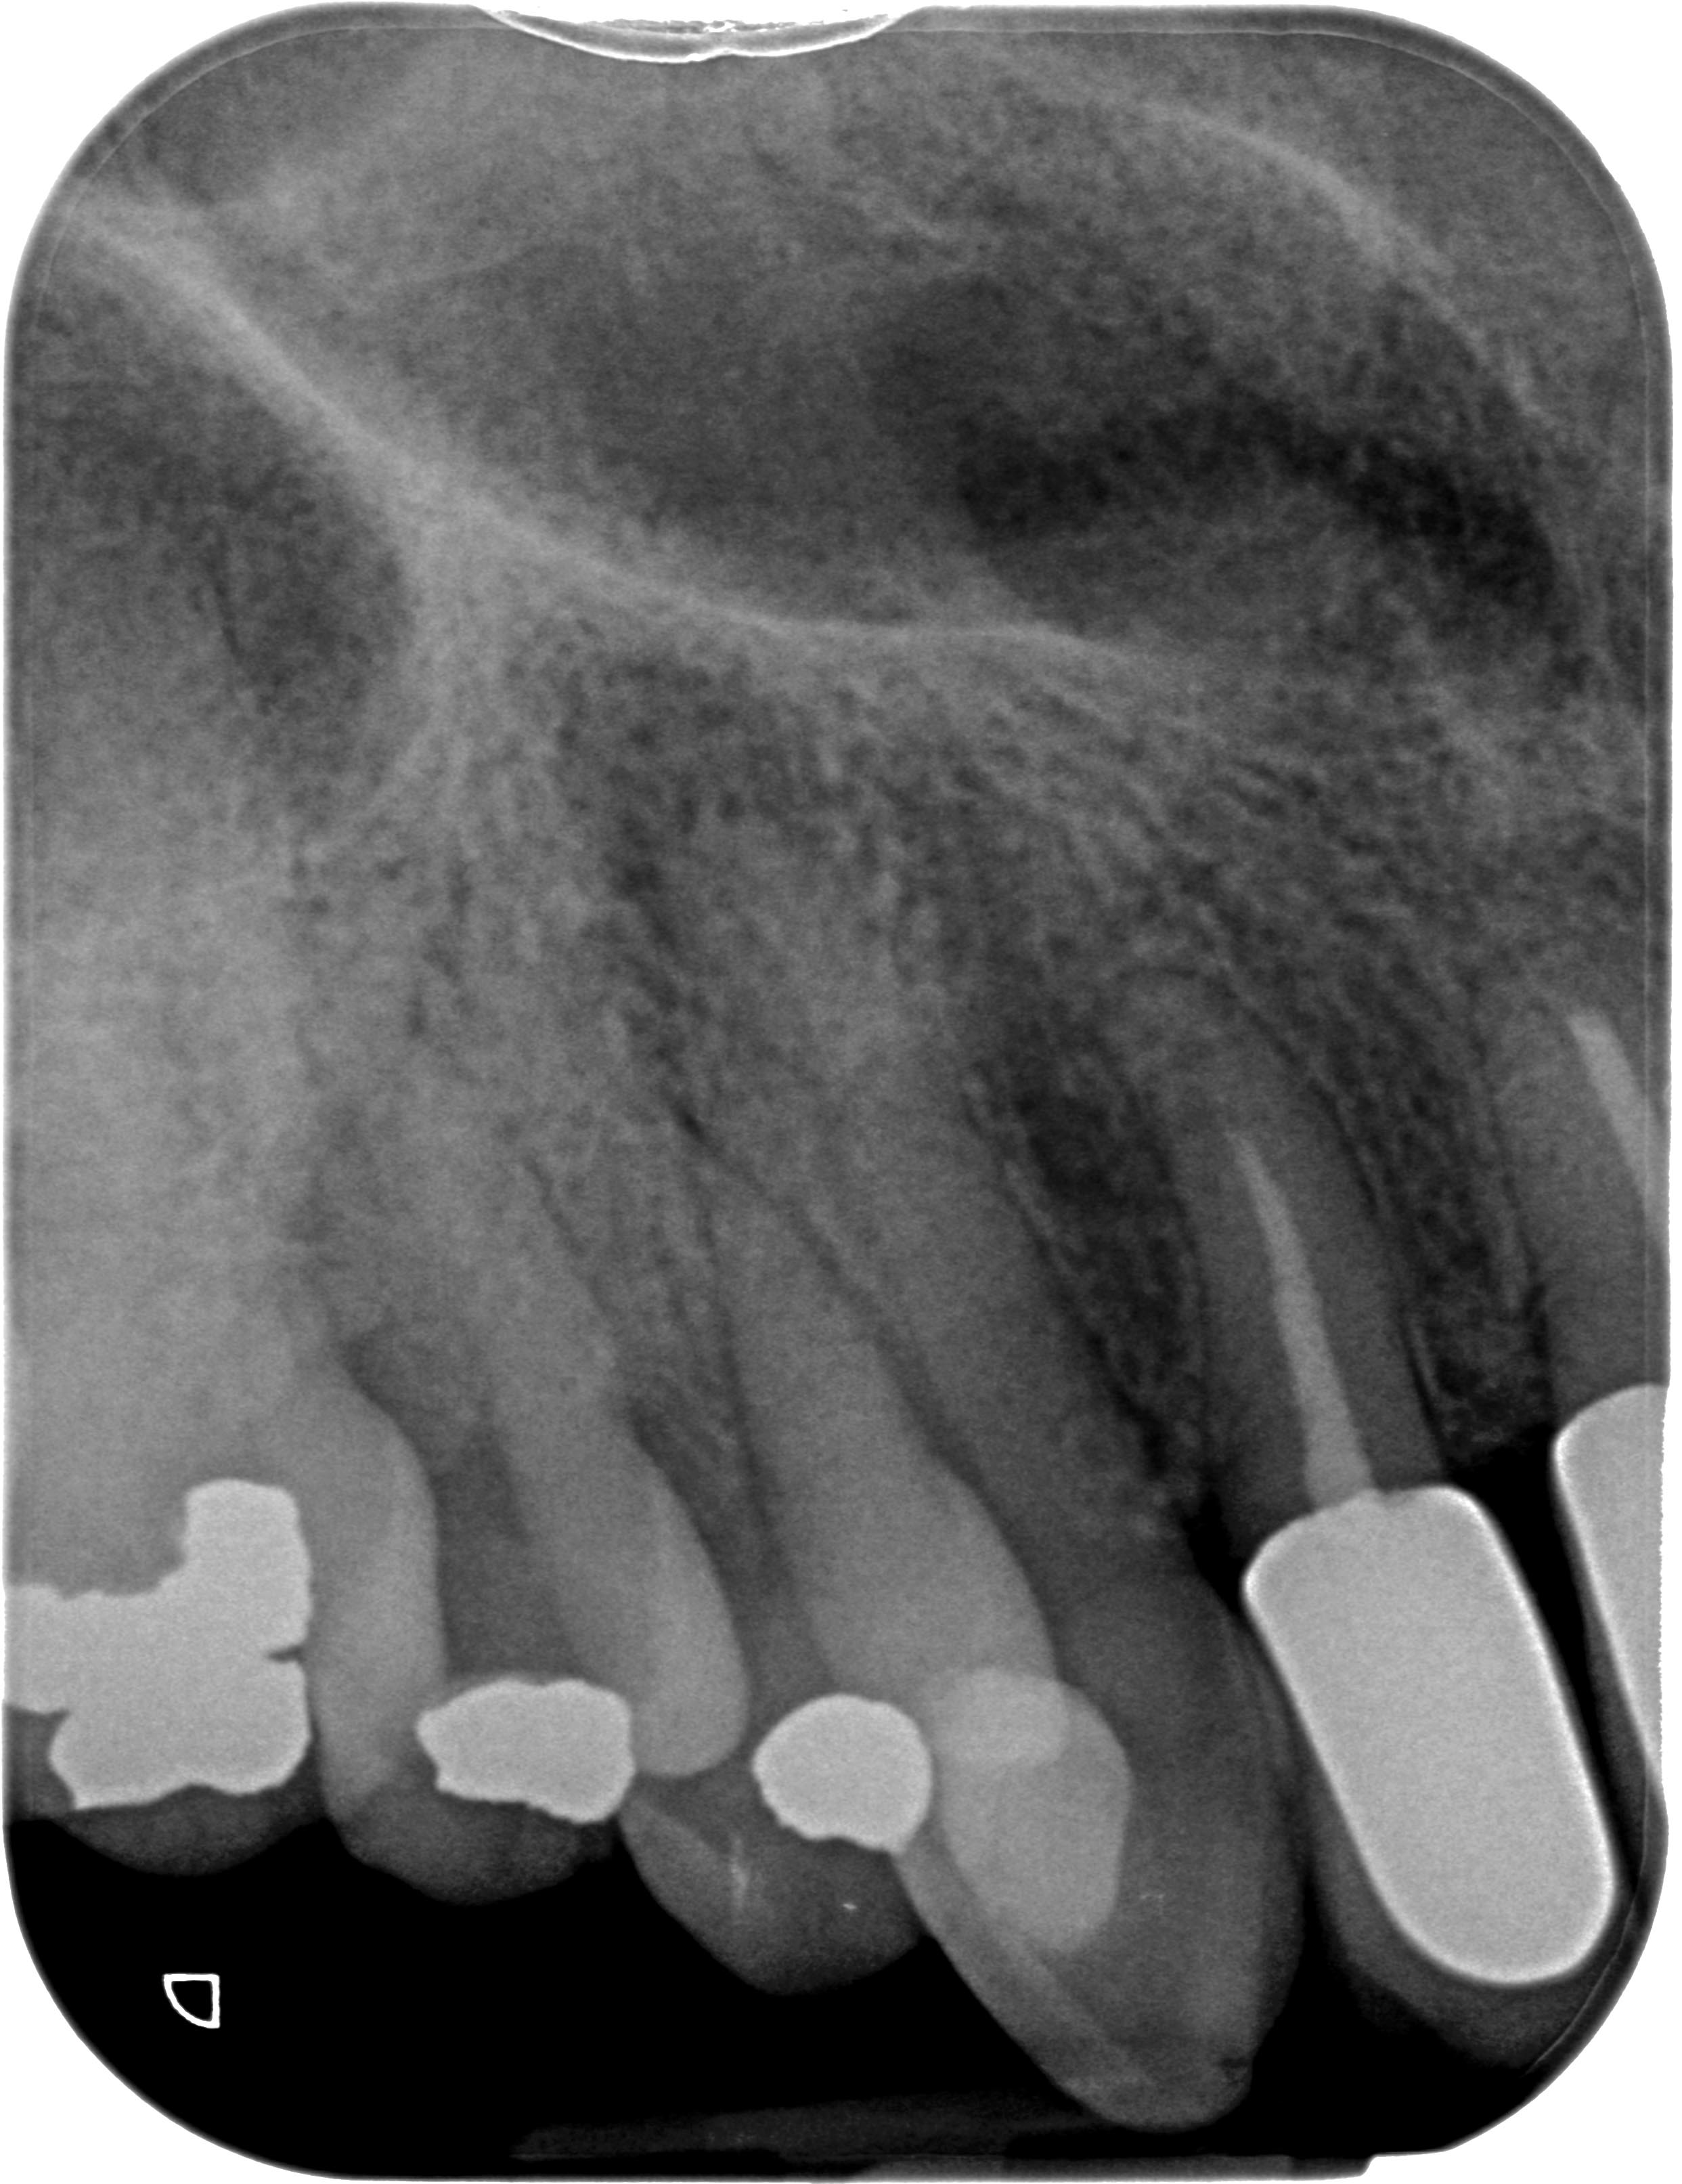

KU13R-1

Neue Wege gehen